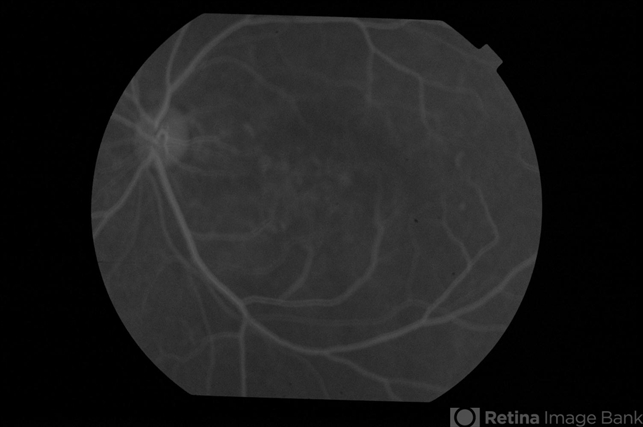

- CSCR subfoveal leak

- Early phase fluorescein angiogram of a 52-year-old male with left eye CSCR of 6 months duration.